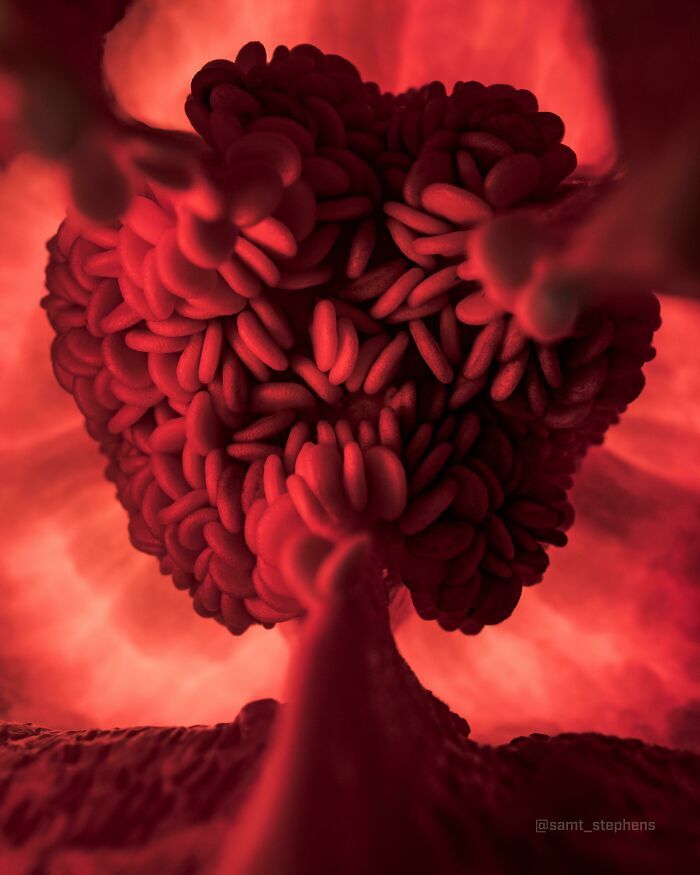

3